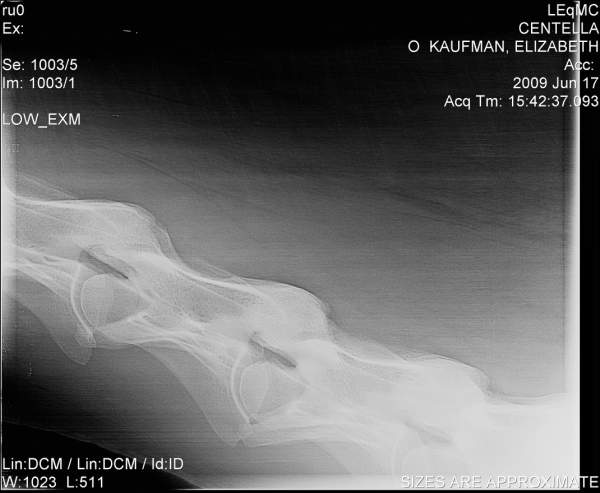

Posted on Thursday, Jun 18, 2009 - 12:01 pm: Hello DrO,I'd be curious to hear your opinion of these cervical radiographs. They are of a 7 yo horse with a history of non-performance with various low grade hind end lamenesses and symmetric poor muscle development. The neuro exam on this horse was "not quite right" on the hind end, though there were no glaring, repeatable failures.

Posted on Friday, Jun 19, 2009 - 8:15 am: Hello elk,Of all skeletal radiographs cervical vertebral radiographs are some of the very hardest to accurately interpret requiring the very best resolution, often over an hour of review with rulers, marking pens, and calculators to determine the significance of perceived irregularities. In the above images many of the facets and spinal canal spaces are not clear enough for a good evaluation. They may be fine on the orignals however. So let me turn this around and ask you did the folks reviewing the originals and hopefully spend the required time to assess the hundreds of individual points of interest in such a radiographic series find any abnormalities? I always think it wise to have such a set of radiographs with questionable findings be reviewed by a equine radiologist or orthopedic surgeon. DrO |

Posted on Friday, Jun 19, 2009 - 9:37 am: Hello DrO,The x-rays were reviewed as carefully as possible, I believe, given the experience and schedules of the folks involved. The originals are somewhat more clear, though not perfect-- it's a very big horse. Conversion to jpeg format and reduction for posting has not improved them! These x-rays also have been referred out for review. The equine surgeon who examined the horse and (with her colleagues) reviewed the x-rays was suspicious that there was evidence of DJD in C5-C7, with C6-C7 being the area most highly compromised. Based on this, the horse has been recommended to be euthanized or retired. If retired, they warned me that he may experience significant degeneration over time (rate of decay unknowable), to the point where he may become unstable or even unable to stand. This working diagnosis is somewhat influenced by the neurologic changes in the sire of the horse, who was stringhalt as he aged (at the time, attributed to neck trauma or old age). Unfortunately, I own 4 horses with these genetics, so I want to be very careful with the diagnosis. We had x-rayed every leg joint in this horse many times, never with an OCD finding elsewhere, though I understand the neck lesions can be found in horses with no other visible DJD. The diagnosis is not implausible given the history and symptoms that took the horse to x-ray. |

Posted on Sunday, Jun 21, 2009 - 10:51 am: elk, sorry for the delay I wanted to view this in my office where I have a large screen high contrast monitor. Hmmmm...the first image, which appears to be a retake of the last image to help bring out the details of C6-C7, does show a step in the articulation of the bodies of C6-C7 but I lose details of the facets and most important the margins of the the vertebral canal. This step may represent the narrowing they are discussing but my lack of regular review of such radiographs makes my interpretation subject to question.DrO |

Posted on Sunday, Jun 21, 2009 - 3:39 pm: Hi DrO, thank you.In the original format on the large viewer at Littleton, the changes you note are even clearer. C6-C7 look almost as if they were starting to fuse, and the canal appears to have narrowed such that it is most probably beginning to impinge on the spinal cord. Do you concur that, if the x-rays have been read correctly, the horse is unsafe to ride? Do you know anything about the origins, management, or progression of this condition? Littleton clearly felt that it would be progressive and eventually fatal, should the horse be left to degenerate indefinitely. They could not speculate on how rapidly that progression might occur, and felt that it was probably similar to other forms of OCD (significantly hereditary, with environmental and management factors as well). |

Posted on Sunday, Jun 21, 2009 - 10:39 pm: I see...I had presumed the loss of definition of the articular facets was with the image size and quality. The way you frame the question it is a easy call elk, if the spinal cord is being impinged, yes the horse should be considered dangerous to ride and the disease most likely progressive.Concerning your questions on origin, management, and progression they are discussed in the article. If you have specific question not covered post it back here. DrO |